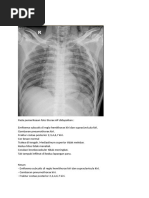

Thorax PA post KLL

Foto Thorax PA view, posisi erect, simetris, inspirasi dan kondisi cukup, hasil:

- Tampak corakan bronchovaskuler normal

- Tak tampak perselubungan semiopaque homogen di aspek laterobasal kedua

hemithorax

- Tak tampak area lusen tanpa corakan vaskuler di kedua hemithorax

- Kedua sinus costophrenicus lancip

- Kedua diafragma licin dan tak mendatar

- Cor, CTR < 0,50

- Sistema tulang yang tervisualisasi intact

Kesan :

- Pulmo tak tampak kelainan

- Besar cor normal

- Tak tampak fraktur pada sistema tulang yang tervisualisasi

- Tak tampak tanda-tanda hydropneumothorax